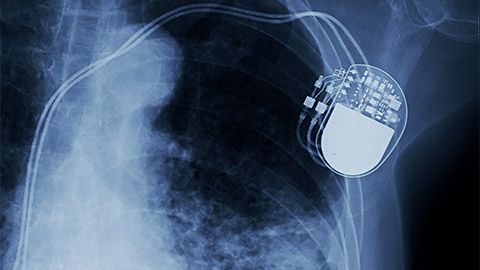

0:01:46.2 RW: Today's I Have a Client Who is on a topic I'm a little surprised we haven't covered here before, working with clients who have pacemakers. Specifically, in this case, a newly installed pacemaker, which makes this decision a little more complicated. I'm going to share this story with you and then provide a little background information on these devices, and then we can evaluate our contributor's decision. They wrote me this letter.

0:09:01.5 RW: But our client in today's story didn't say anything about a history of a heart attack. Huh? Does she really need a pacemaker? Well, we'll get back to that in a moment. Pacemakers have been around for decades. About 350,000 Americans get one every year, and they come in three main varieties. There's one that's implanted directly into the heart muscles with no wires or pulse generator; and there's one with a pulse generator just under the skin on the chest that's connected to a single insulated wire that's called a lead and that lead connects to the targeted ventricle with an electrode; and there's a version with two leads going to whichever chambers need to be reorganized. During the insertion procedure, the leads are threaded through an artery or a vein to reach the right section of the heart. Both of these types of pacemakers involve a pulse generator that is located just under the skin below the clavicle. This is where the pacemaker battery is located. And those batteries last for 10-15 years, and replacing them is fairly simple.

0:10:08.0 RW: After a few months, scar tissue grows all around the leads and makes them extremely stable. They really don't budge. And that's why the common wisdom is that massage or sports or other activities are safe at this point. Getting a pacemaker is not risk free, as you can imagine. People can develop blood clots, they can have blood vessel damage or infections, sometimes much more serious complications come up, they're pretty rare. There's also a situation called pacemaker syndrome, where doctors are unable to establish good coordination of the heart muscle regardless of how the device is used. Also, a person with a pacemaker can't receive an MRI, they might set off metal detectors at the airport, and they have to avoid having any magnets near their chest.